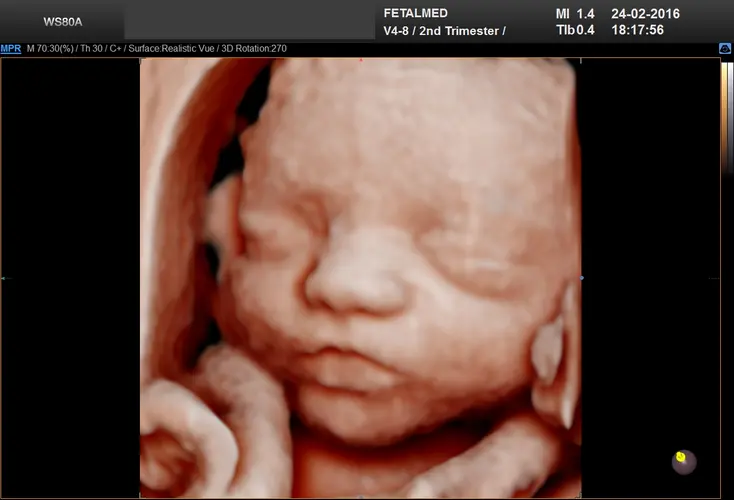

Nesta semana, seu bebê está ganhando peso de forma impressionante, acumulando aproximadamente 225 gramas semanalmente. Ele já pesa entre 1,9 e 2,1 quilos e mede cerca de 43 a 44 centímetros da cabeça aos pés. Este crescimento acelerado é fundamental para o desenvolvimento dos órgãos e sistemas que ainda precisam amadurecer antes do nascimento.

Os movimentos fetais atingem seu pico de intensidade nesta fase da gravidez. Com o espaço cada vez mais restrito no útero, seus chutes e socos podem ser bastante desconfortáveis para você. O líquido amniótico atingiu seu volume máximo, o que significa que há menos “almofada” para amortecer os movimentos do bebê. É normal que você sinta claramente quando ele muda de posição ou se alonga.

Sua barriga agora exibe movimentos visíveis que podem ser fascinantes de observar. Você pode ver pequenas ondulações se movendo de um lado para o outro quando o bebê se mexe. Com o espaço reduzido, muitas vezes é possível distinguir diferentes partes do corpo do bebê apenas tocando suavemente a barriga – você pode conseguir identificar se está sentindo uma mão, um pé ou até mesmo o joelhinho dele.